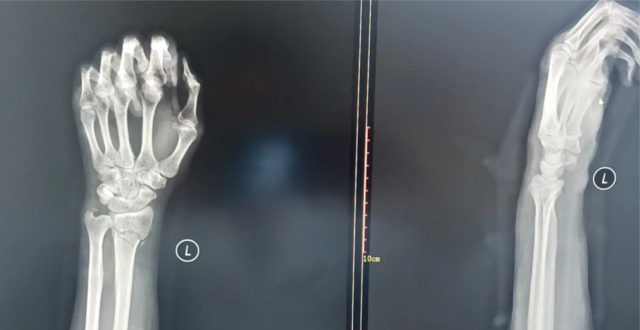

开始工作的第一周,骨科收治了一名桡骨远端骨折患者。男性,42岁,是家里唯一的“顶梁柱”,可是家庭条件并不富裕。韩建明主任仔细查看患者影像学检查资料后,结合患者经济状况,针对性地制定了压垫和小夹板结合的保守治疗方案。

经过韩主任短短数分钟的牵拉及手法复位,纠正了患者的腕部畸形,局部血肿逐渐消散。

第二天复查X光片,治疗效果满意,韩主任耐心叮嘱其出院后注意事项,嘱咐定期门诊复查,患者及家属连连感谢。

▲ 手法复位前X光片

▲ 手法复位后X光片